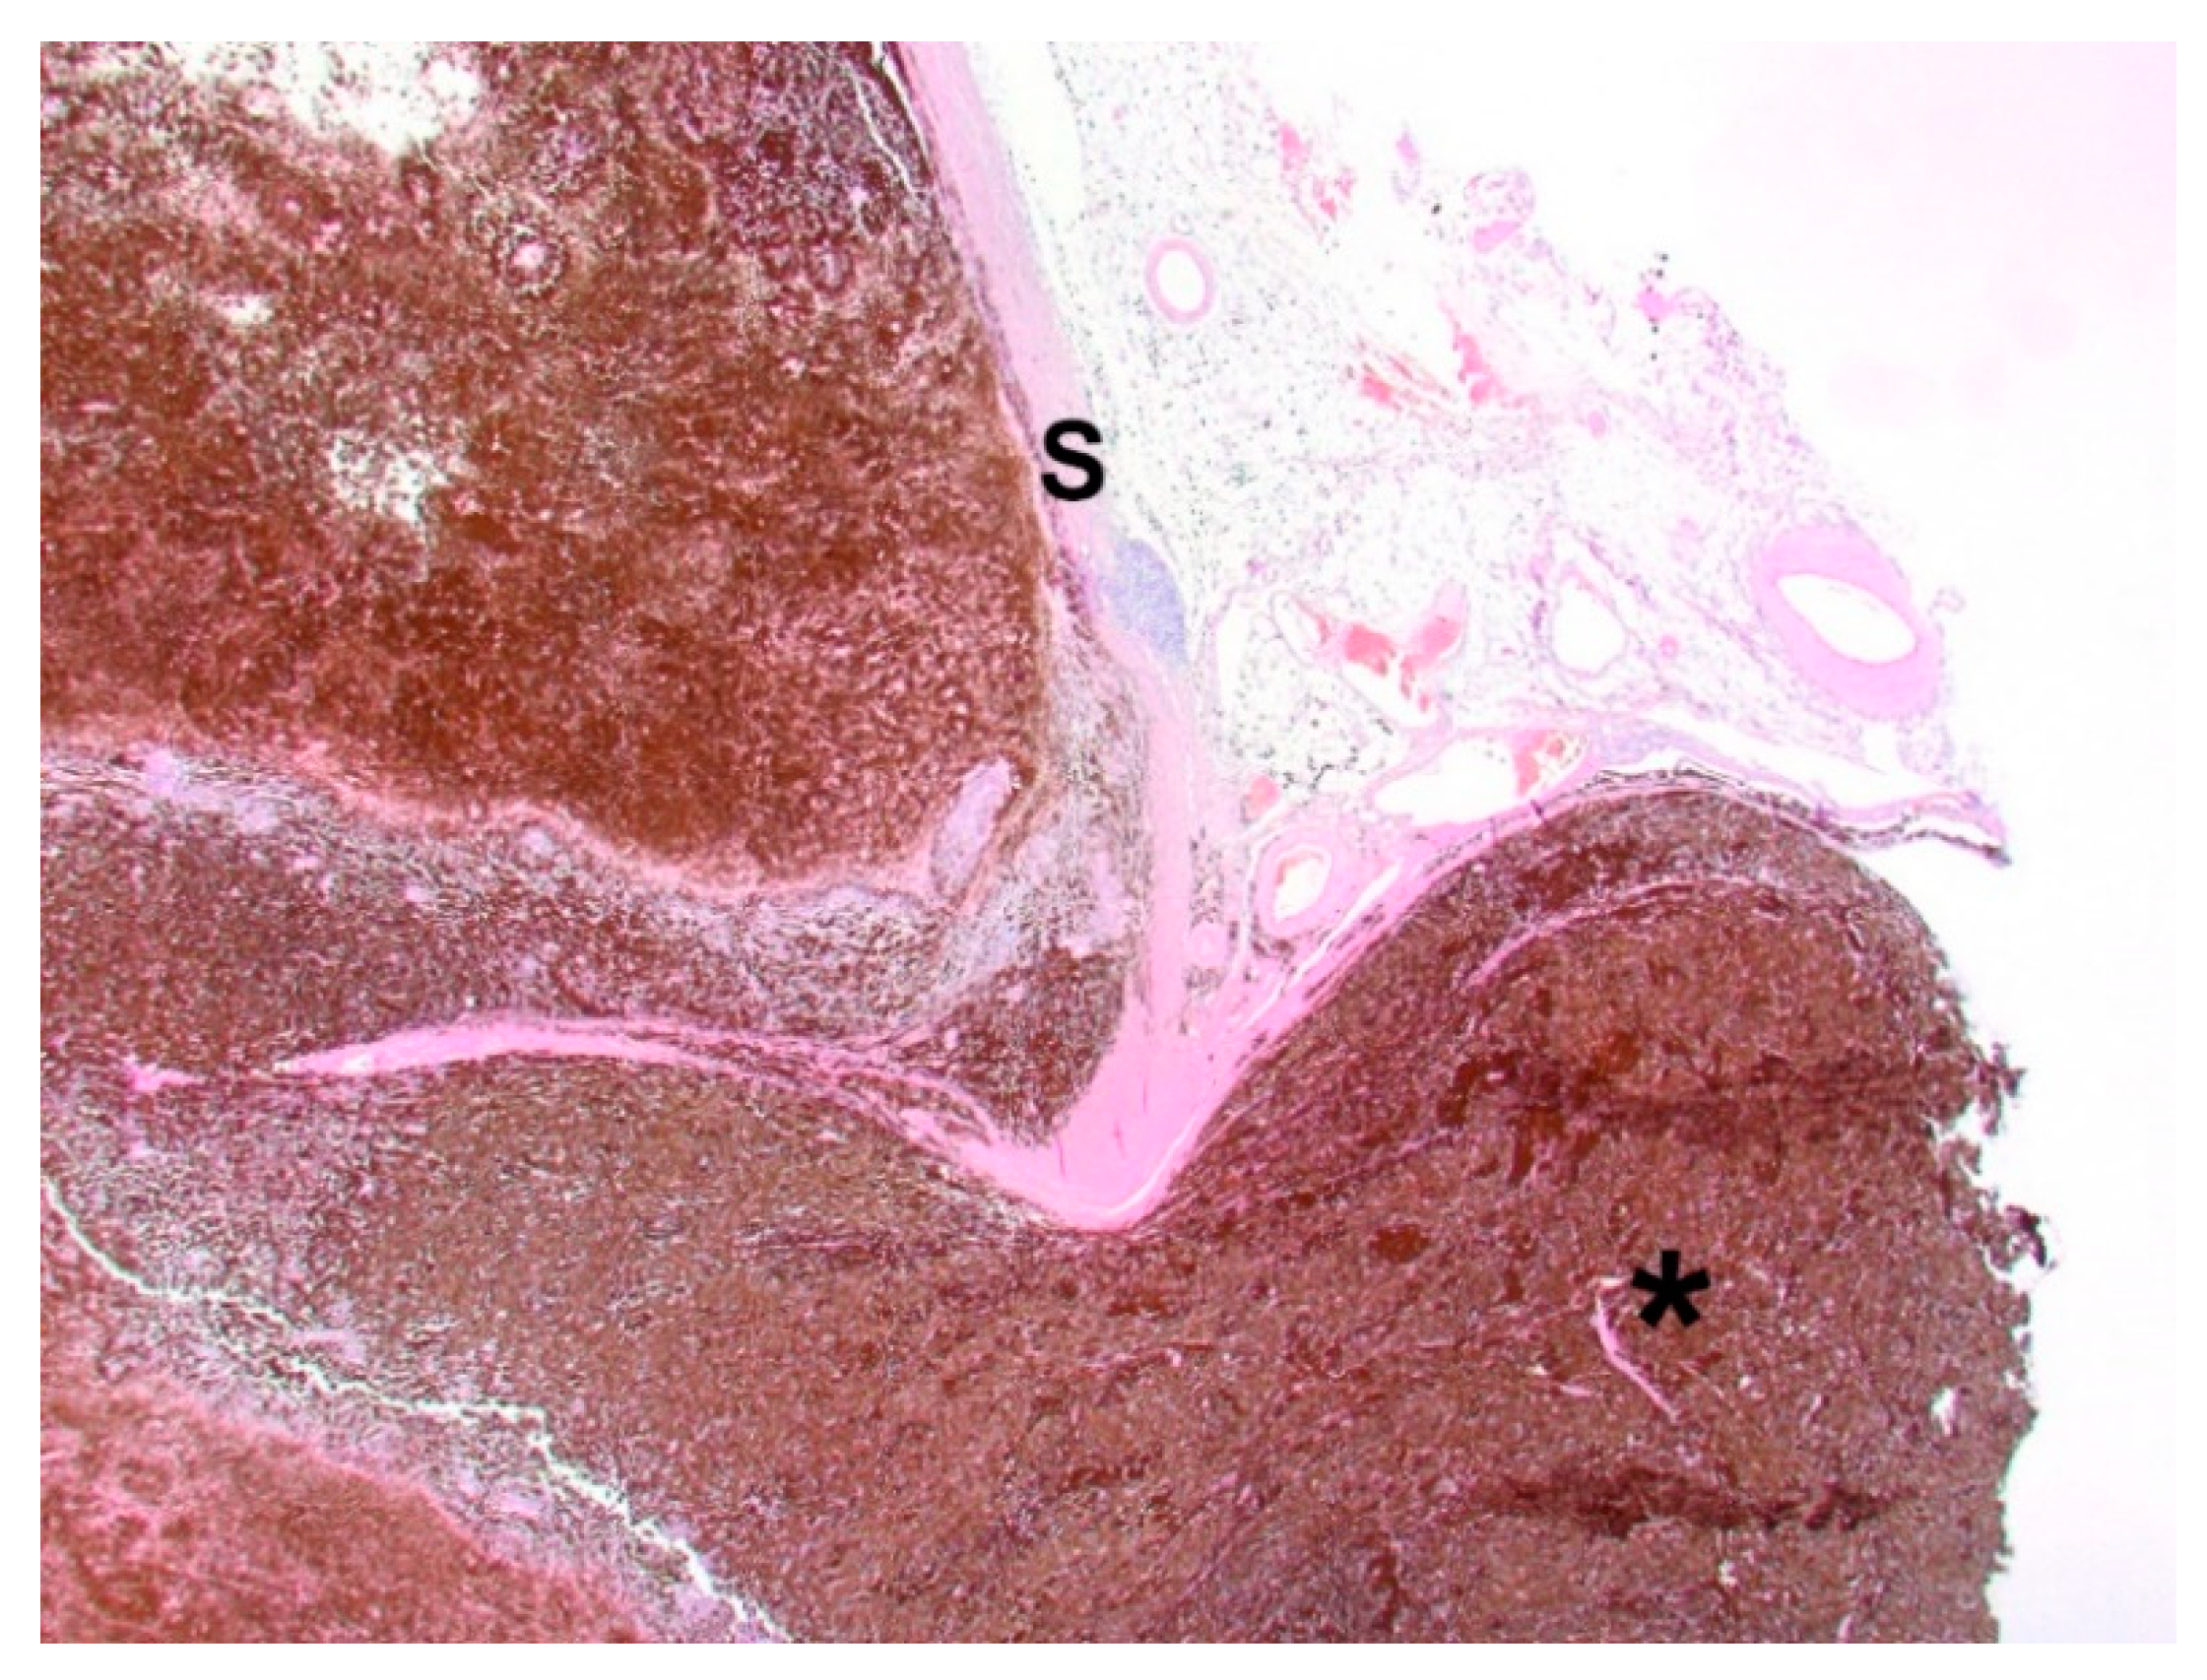

The bulbus, as well as three tumor bed biopsies, was fixed in 10% buffered formalin and sent to the Specialized Practice for Veterinary Pathology in Munich, Germany. Figure 4 represents the cross-section of the bulbus. The dark mass showed extensive infiltration of the intraocular chambers. Posterior extension of the tumor in the area of the optic disc was already visible macroscopically. A cross-section from the bulbus and lens and three tumor bed biopsies were paraffin-embedded, microtome-sectioned and hematoxylin-eosin-stained. Bleaching was performed to remove melanin pigment and to demonstrate cellular morphology more clearly.

The histopathological investigation revealed a choroidal melanocytoma with partial infiltration of the sclera and optic disc, and perineural retrobulbar extension (Figure 5). The cross-section showed a diffuse infiltration with two different cell types: one plump, heavily pigmented population and a second spindle cell type of melanocytic cells. In the bleached sections (Figure 6), the two cell types showed a round to oval nucleus, respectively, and the majority of one nucleolus was visible. No significant atypia and very low mitotic activity, less than 4 mitoses in 10 high-power fields (HPF), were observed. The plump, pigmented cells could be found in the periphery of the optic nerve. No vascular invasion was found. The tumor bed biopsies confirmed retrobulbar spreading in one of the three specimens. There were pigmented cells without atypia, loosely interspersed and partly more densely packed between the skeletal musculature and the local adipose tissue.

Figure 5. Choroidal melanocytoma with infiltration of the optic disc and extension along the optic nerve (star); S: sclera. Hematoxylin and eosin. 100× magnification.